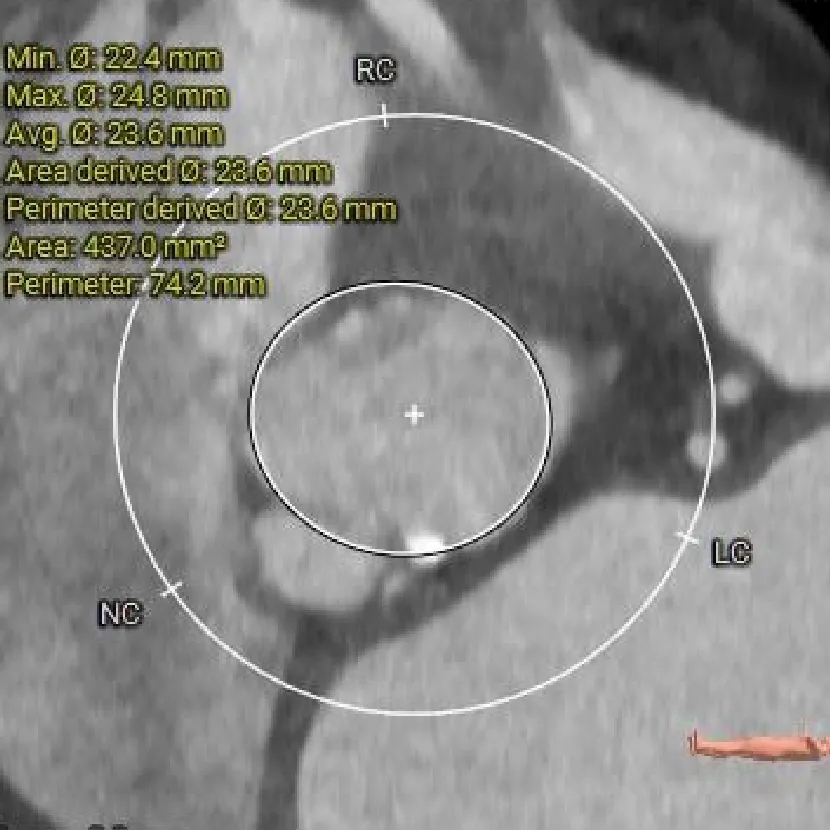

瓣上2mm

23.6mm